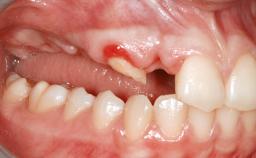

Shell Technique for Horizontal and Vertical Maxillary Bone Augmentation in a Partially Edentulous Patient with Aggressive Periodontal Disease

A 46-year-old woman was referred for treatment whose main complaints were mobility of her fixed partial dentures (right maxilla and left mandible) and periodontal bleeding during function. She also reported having taken systemic antibiotics to treat recurrent swelling in the area of the upper left molars. The patient had not seen a dentist for at least 2 years. She did not smoke and had no history of major systemic disease other than two minor orthopedic procedures some years back. The first-visit examination revealed poor plaque control, tooth mobility, periodontal disease, and a residual dentition widely associated with deep periodontal pockets.

Bone Augmentation Horizontal|Staged|Vertical

Bone Volume Horizontally and vertically sufficient Horizontally deficient Deficient vertically or deficient vertically AND horizontally

Bone Volume Deficient vertically or deficient vertically AND horizontally